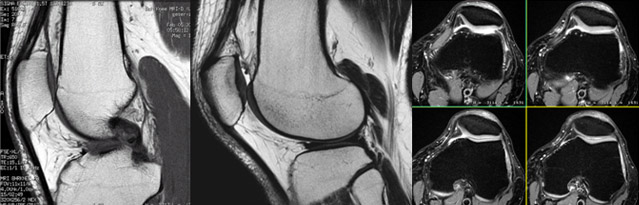

MRI Knee joint

หัวเข่าเป็นข้อที่รับน้ำหนักของร่างกายและเคลื่อนไหวเพื่อให้เราเดิน ลุก นั่ง นอน ได้ ข้อเข่ายังทำหน้าที่เป็นตัวลดแรงกระแทกจากการวิ่งหรือกระโดดโดยการผ่อนถ่ายน้ำหนักของร่างกายอีกด้วย ข้อเข่าจึงเปรียบได้กับส่วนโช๊คอัพ ของรถยนต์ เมื่ออายุมากขึ้น ข้อเข่าที่ทำงานมานานก็มีโอกาสเกิดโรคเข่าเสื่อม ปวดข้อ ข้อบวม สำหรับผู้ที่เล่นกีฬาหรือได้รับการบาดเจ็บของข้อเข่าจากอุบัติเหตุ เส้นเอ็นหรือกระดูกอ่อนในข้อเข่าก็จะฉีดขาดได้ ทำให้มีเลือดออกในข้อเข่า เจ็บปวดเรื้อรัง และไม่สามารถขยับข้อเข่าได้ตามปกติ เมื่อเกิดความผิดปกติที่ข้อเข่า แพทย์จะตรวจดูว่าข้อเข่าโดยการให้ผู้ป่วยขยับข้อเข่าไปมาลองกดดูว่ามีความเจ็บปวดที่จุดใดหรือด้านใดบ้างเพื่อเป็นตัวบ่งชี้ว่าจะมีการบาดเจ็บเส้นเอ็นหรือกระดูกอ่อนฉีดขาดหรือไม่หากสงสัยแพทย์มักจะส่งตรวจเอกซเรย์ข้อเข่าเพื่อดูกระดูกว่ามีกระดูกหักหรือความเสื่อมของกระดูกหรือไม่และส่งตรวจ เอ็ม.อาร์.ไอ. เพื่อดูสภาพกระดูกและเส้นเอ็นในข้อเข่าการตรวจ เอ็ม.อาร์.ไอ. ข้อเข่ไม่มีความเจ็บปวดแต่อย่างใดเพียงแค่นอนหงายบนเครื่อง จากนั้นจะมีเครื่องรับสัญญาณมาวางครอบหัวเข่าไว้ ขาทั้ง 2 ข้าง และหัวเข่าจะเคลื่อนเข้าสู่เครื่องตรวจส่วนศีรษะจะอยู่นอกเครื่องตรวจทำให้

ท่านไม่อึดอัดท่านสามารถอ่านหนังสือหรือฟังเพลงได้ขณะตรวจด้วย เอ็ม.อาร์.ไอ. ถือว่าเป็นเครื่องมือที่ให้ภาพของกระดูก เส้นเอ็นและกระดูกอ่อนในข้อเข่าที่ชัดเจนมากโดยที่ผู้ป่วยไม่ต้องเจ็บตัว การตรวจสามารถทำได้ง่ายโดย การนอนในท่านอนหงายบนเตียงตรวจเจ้าหน้าที่จะนำอุปกรณ์รับสัญญาณคลื่นแม่เหล็กมาวางไว้บริเวณเข่า เตียงตรวจเคลื่อนเข้าตรวจในเครื่อง เอ็ม.อาร์.ไอ. เฉพาะบริเวณหัวเข่าทำให้ท่านไม่รู้สึกอึดอัด การตรวจใช้เวลาประมาณ 30 นาที

การตรวจด้วยเครื่อง MRI ของหัวเข่า นั้นมีข้อดีเหนือกว่าการ X-RAYS มากเพราะนอกจากจะสามารถบอกลักษณะของกระดูกหัวเข่าแล้วเมื่อสงสัยว่าจะมีการฉีกขาดของเส้นเอ็นหรือกระดูกอ่อนภายในข้อจะบอกได้ยัง

สามารถบอกถึงกล้ามเนื้อ เส้นเอ็นและกระดูกอ่อนที่รองรับกระดูกหัวเข่าชิ้นบนและล่าง

รวมทั้งลักษณะและปริมาณของน้ำในข้อเข่าได้อีกด้วย จึงเป็นประโยชน์อย่างยิ่งในการวางแผนการรักษาต่อไป ซึ่งนอกเหนือจากการตรวจด้วย เอ็ม.อาร์.ไอ. แล้วจะไม่วิธีตรวจใดๆ ที่จะให้ข้อมูลได้มากเที่ยบเท่าได้เลยนอกจากข้อเข่าแล้วยังสามารถตรวจข้อไหล่ ข้อศอก ข้อมือ ข้อนิ้ว ข้อตะโพก ข้อเท้า ได้ด้วย